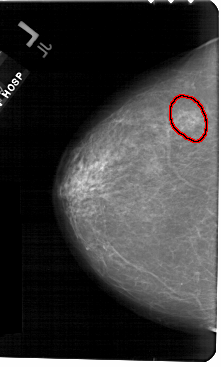

A_1562_1.RIGHT_CC

RIGHT_CC LINES 5266 PIXELS_PER_LINE 3226 BITS_PER_PIXEL 12 RESOLUTION 43.5 NON_OVERLAY

FILE: A_1562_1.LEFT_CC.OVERLAY

TOTAL_ABNORMALITIES 1

ABNORMALITY 1

LESION_TYPE CALCIFICATION TYPE AMORPHOUS DISTRIBUTION CLUSTERED

ASSESSMENT 4

SUBTLETY 3

PATHOLOGY BENIGN

TOTAL_OUTLINES 1